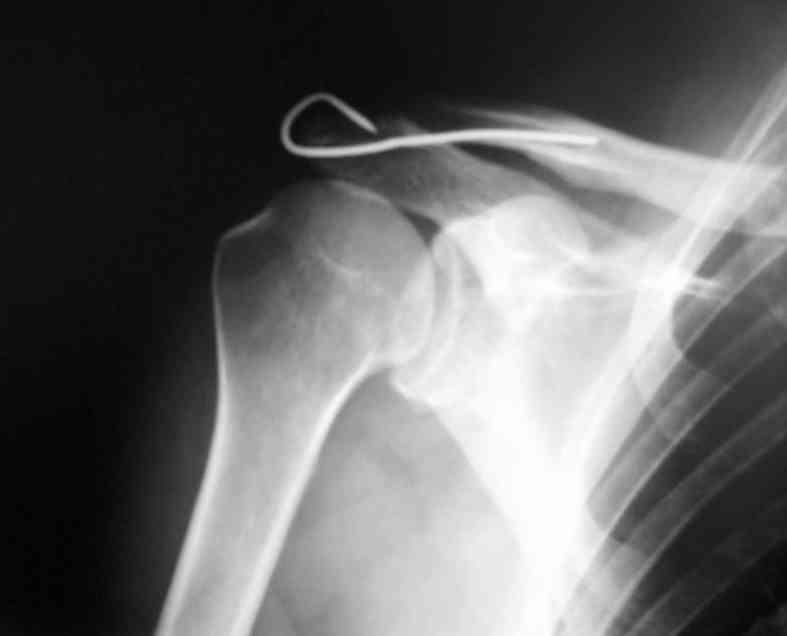

[Ortho] Вывих акромиального конца ключицы

Здравствуйте.Извиняюсь за задержку. Фотографии фиксации АКС. Канал для

ножки фиксатора формируется затупленным шилом, для уменьшения опасности

перфорации кортикального слоя.

В некоторых клиниках активно применяли конструкции из никелида титана (с

термомеханической памятью) с фиксацией за ключицу и клювовидный

отросток. Сам не применял, но отзывы были хорошие а рентгенограммы красивые.